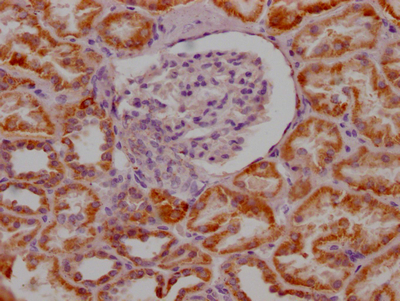

IHC image of CSB-RA250615A0HU diluted at 1:100 and staining in paraffin-embedded human kidney tissue performed on a Leica BondTM system. After dewaxing and hydration, antigen retrieval was mediated by high pressure in a citrate buffer (pH 6.0). Section was blocked with 10% normal goat serum 30min at RT. Then primary antibody (1% BSA) was incubated at 4℃ overnight. The primary is detected by a Goat anti-rabbit IgG polymer labeled by HRP and visualized using 0.05% DAB.